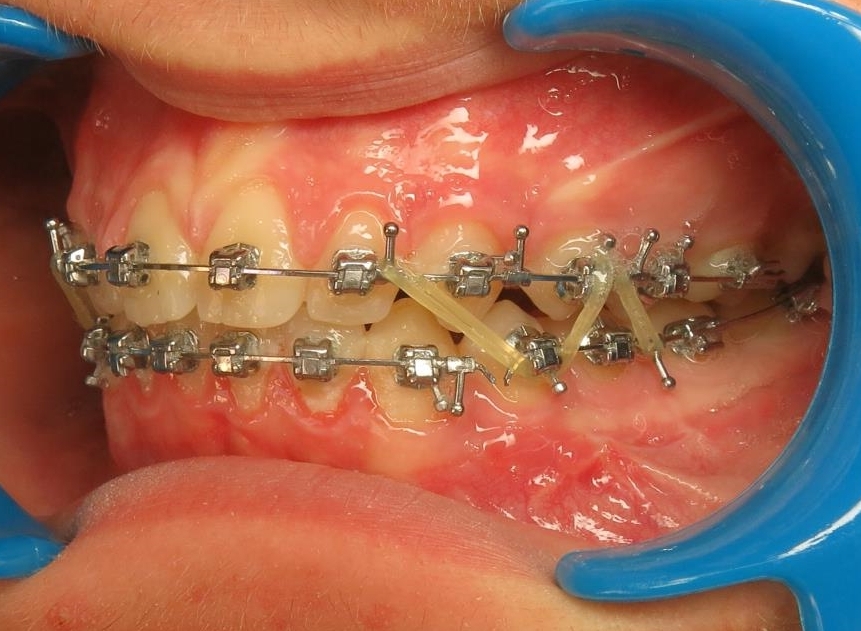

2 - Préparation orthodontique et résultat après chirurgie

Les photos supérieures montrent les arcades juste avant la chirurgie, avec un alignement complet et des axes dentaires physiologiques. La largeur de l’arcade maxillaire a été préparée pour permettre un emboîtement optimal après l’avancée mandibulaire. En bas, les photos post-opératoires montrent des arcades désormais coordonnées, avec une occlusion stable et harmonieuse, grâce à une préparation rigoureuse en amont de l’intervention chirurgicale.